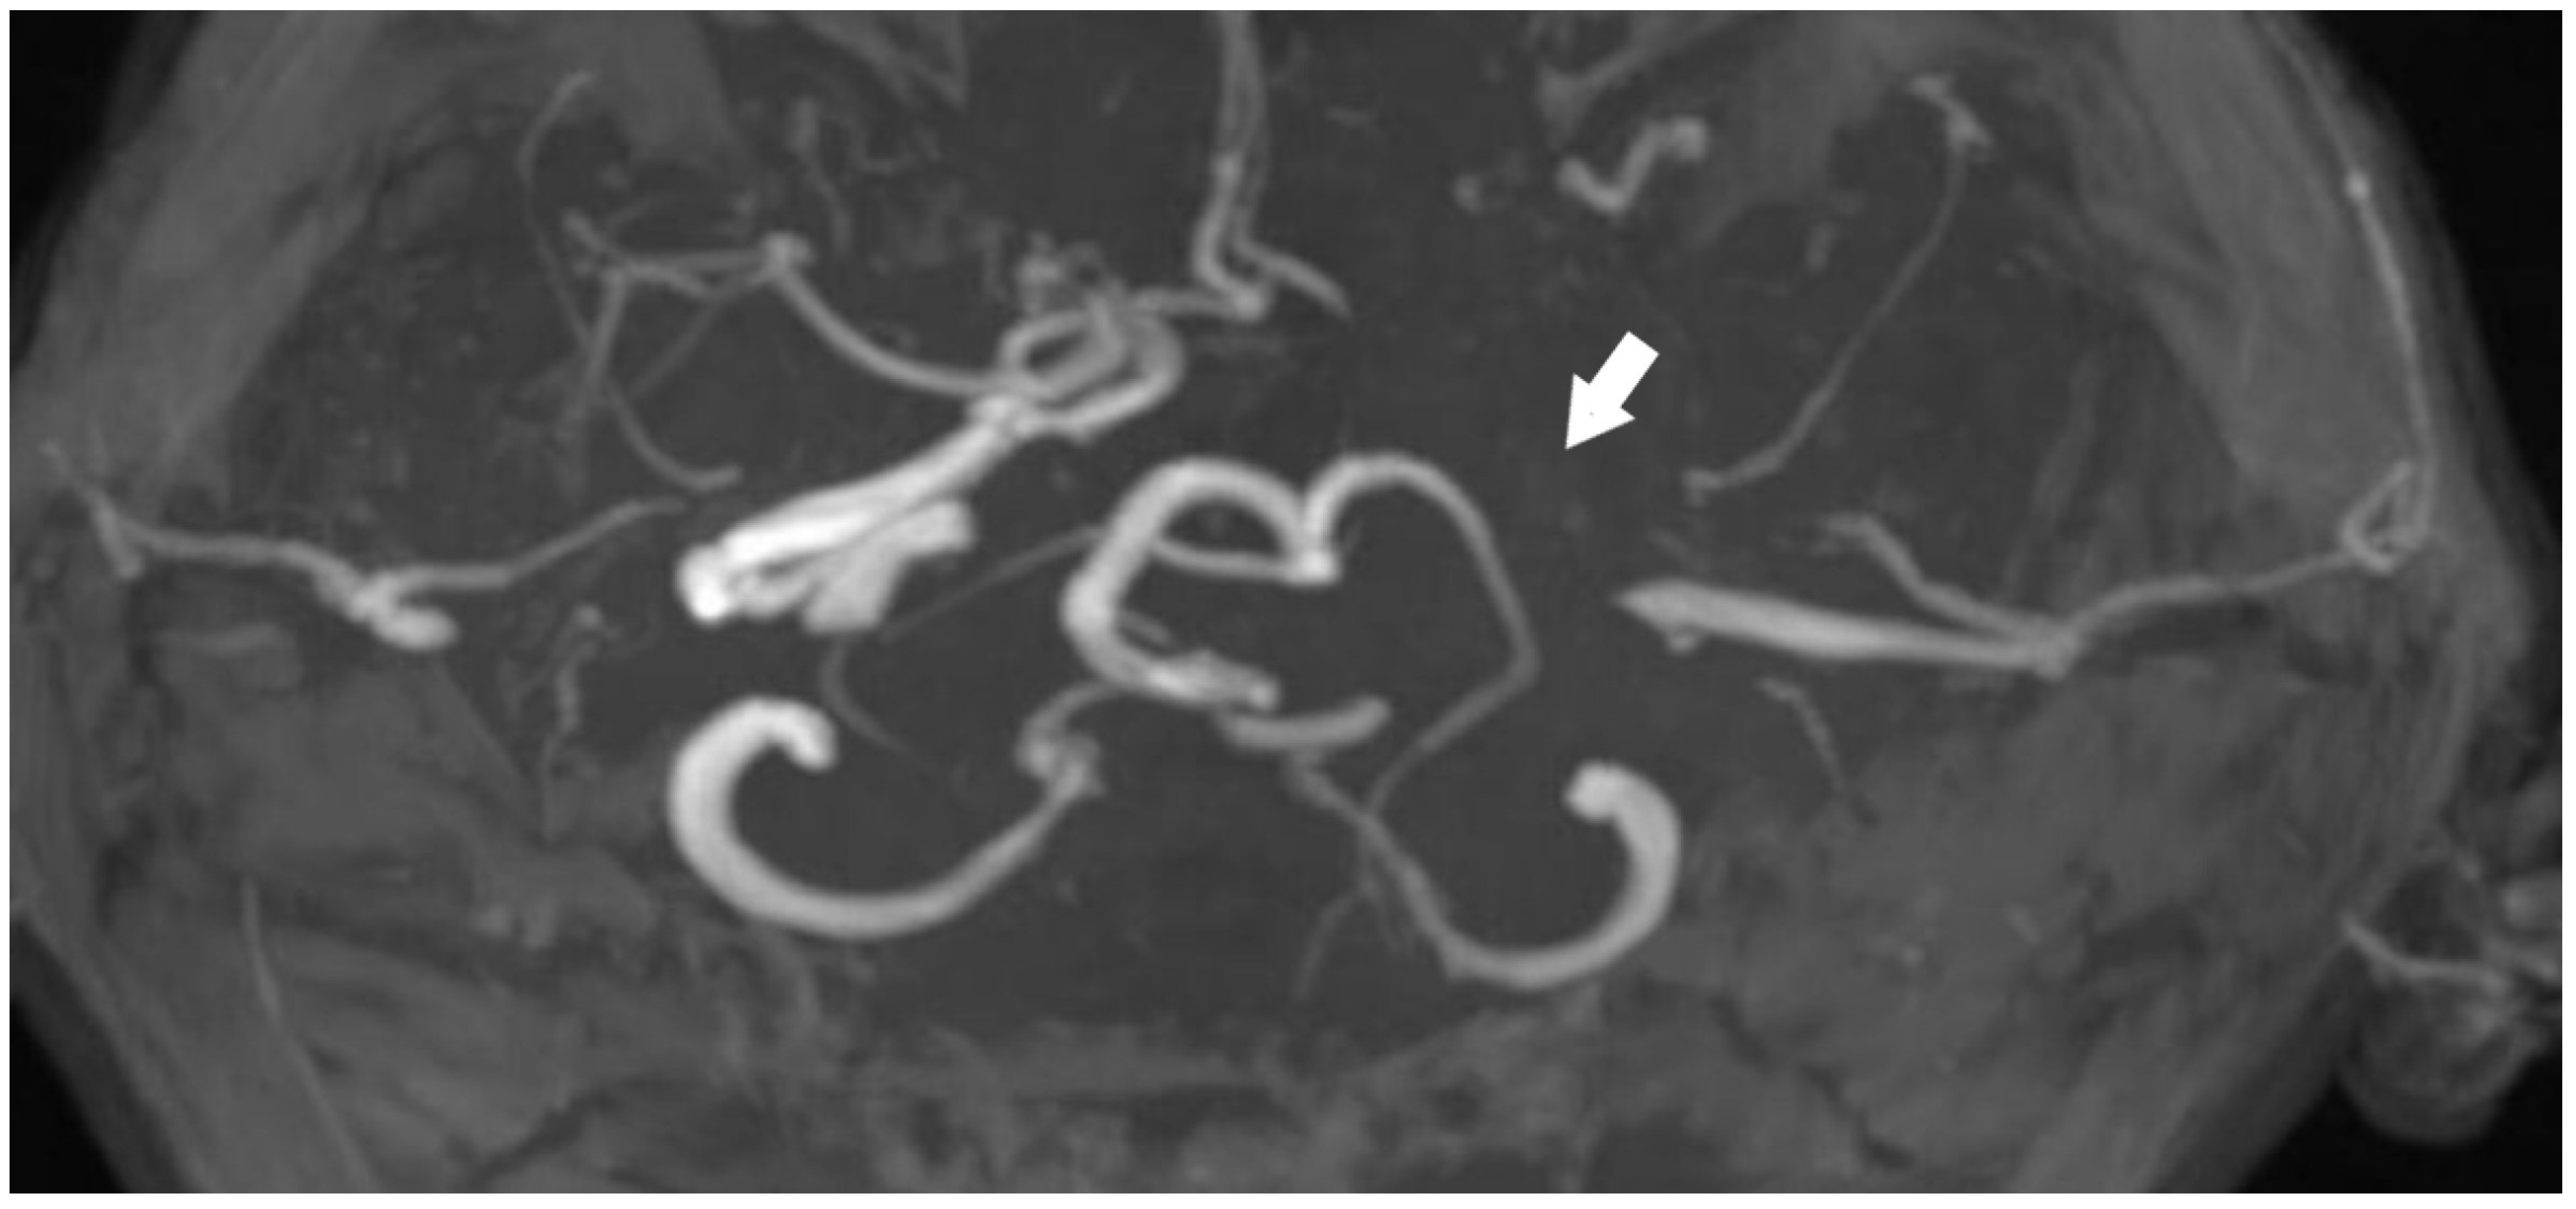

The anterior circulation has been supplied via the anterior communicating artery, while the posterior circulation has received perfusion through the posterior communicating artery (Figure 3).

Figure 3.

Anterior communicating artery [Red arrow] and posterior communicating artery [Yellow arrow], along with the vascular supply to the left hemisphere [TOF images].